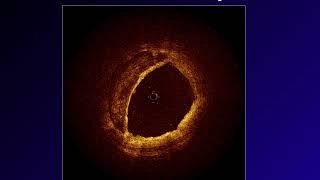

OCT for Identifying vulnerable plaque and guiding PCI, #ACS,#vulnerable,#plaque,#PCI,#rupture,#MI,

What are vulnerable plaque which lead to ACS?#ACS,#vulnerable,#plaque,#PCI,#rupture,#OCT,#cardiology

The Vulnerable Plaque: Poor Healing, Inadequate Angiogenesis.#ACS,#vulnerable,#plaque#PCI,#rupture,

OCT Why?#OCT#Brezinski#Fuimoto#plaque#ophthalmology#stent#macular#GI#MIT